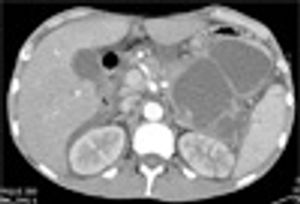

A 38-year-old man with a history of alcoholism, intravenous drug use, and cerebrovascular accident was referred for assessment of possible endocarditis, based on history, fever 39 °C (102.9 °F) and mildly elevated troponin level.